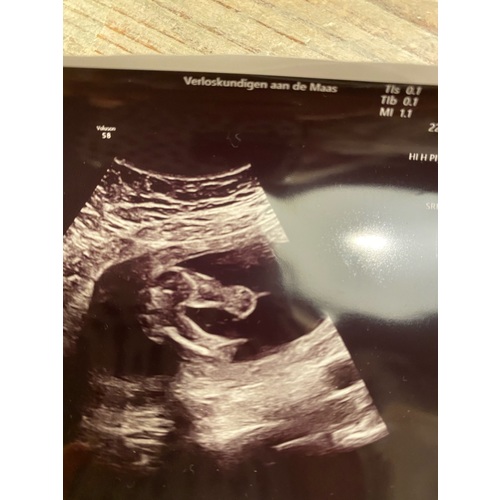

Ik denk ook een jongen! Wat denken jullie van deze echo van 17 weken? Morgen hopelijk bij de 20 weken echo echt bekend wat het wordt :-)

Ik zie hier niets tussen de beentjes. Ik denk dus een meisje. Vertelde je echoscopiste niet over het het geslacht?

Nou bij 11 weken werd een jongen gedacht (hele grote kans zei ze op basis van de nub theorie) en bij 17 weken (de echo die ik stuurde) een meisje, maar deze verloskundige had nog geen echo opleiding afgerond. Voor ons is het nu dus 50/50, maar morgen hebben we de 20 weken echo. Hopelijk dan uitsluitsel :-)